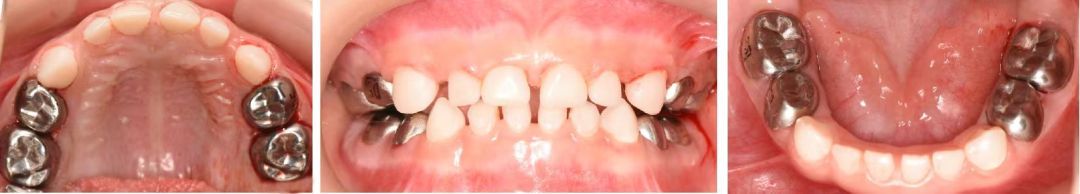

小邓口腔治疗后的照片